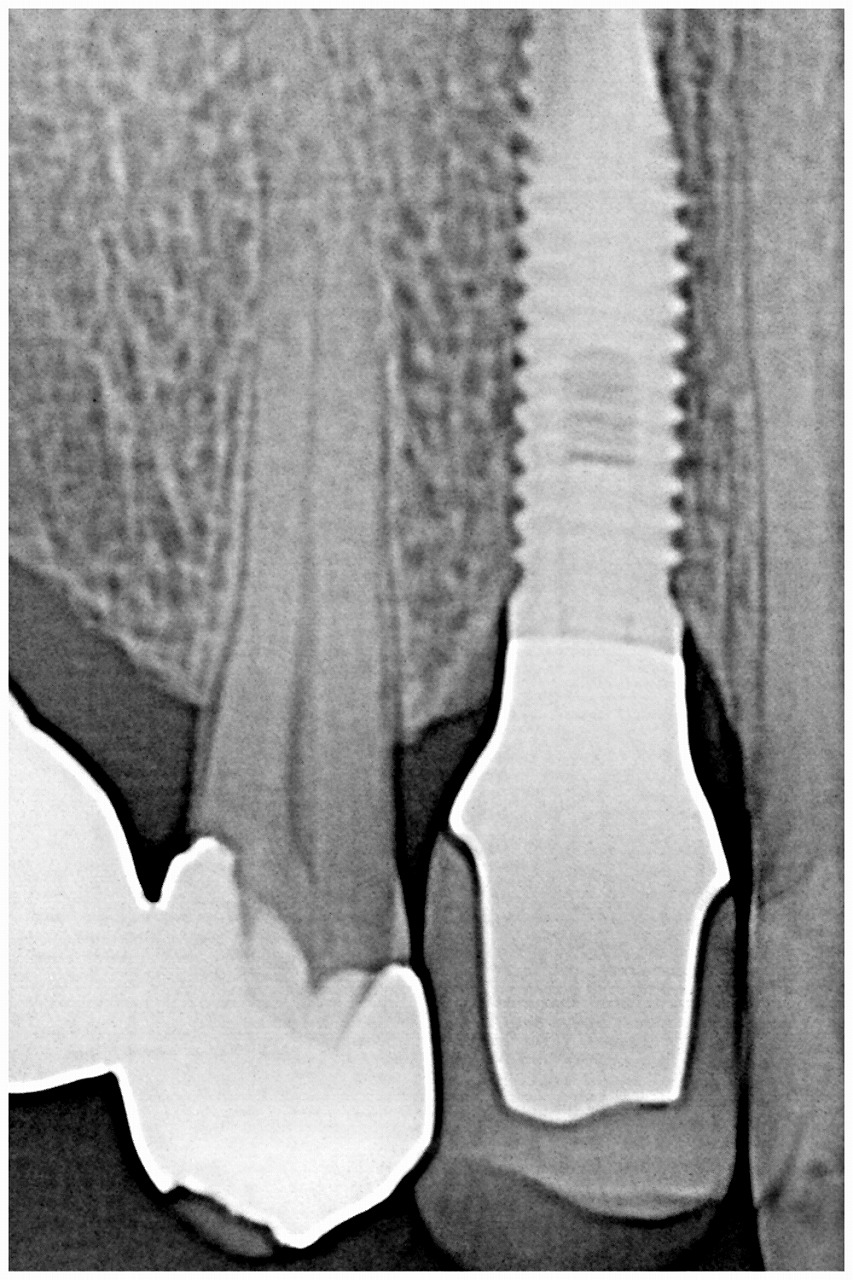

近心部に穴が開いていました

抜歯を行っていきました

抜歯即時インプラント埋入を行っていきました

骨補填材を転入していきました